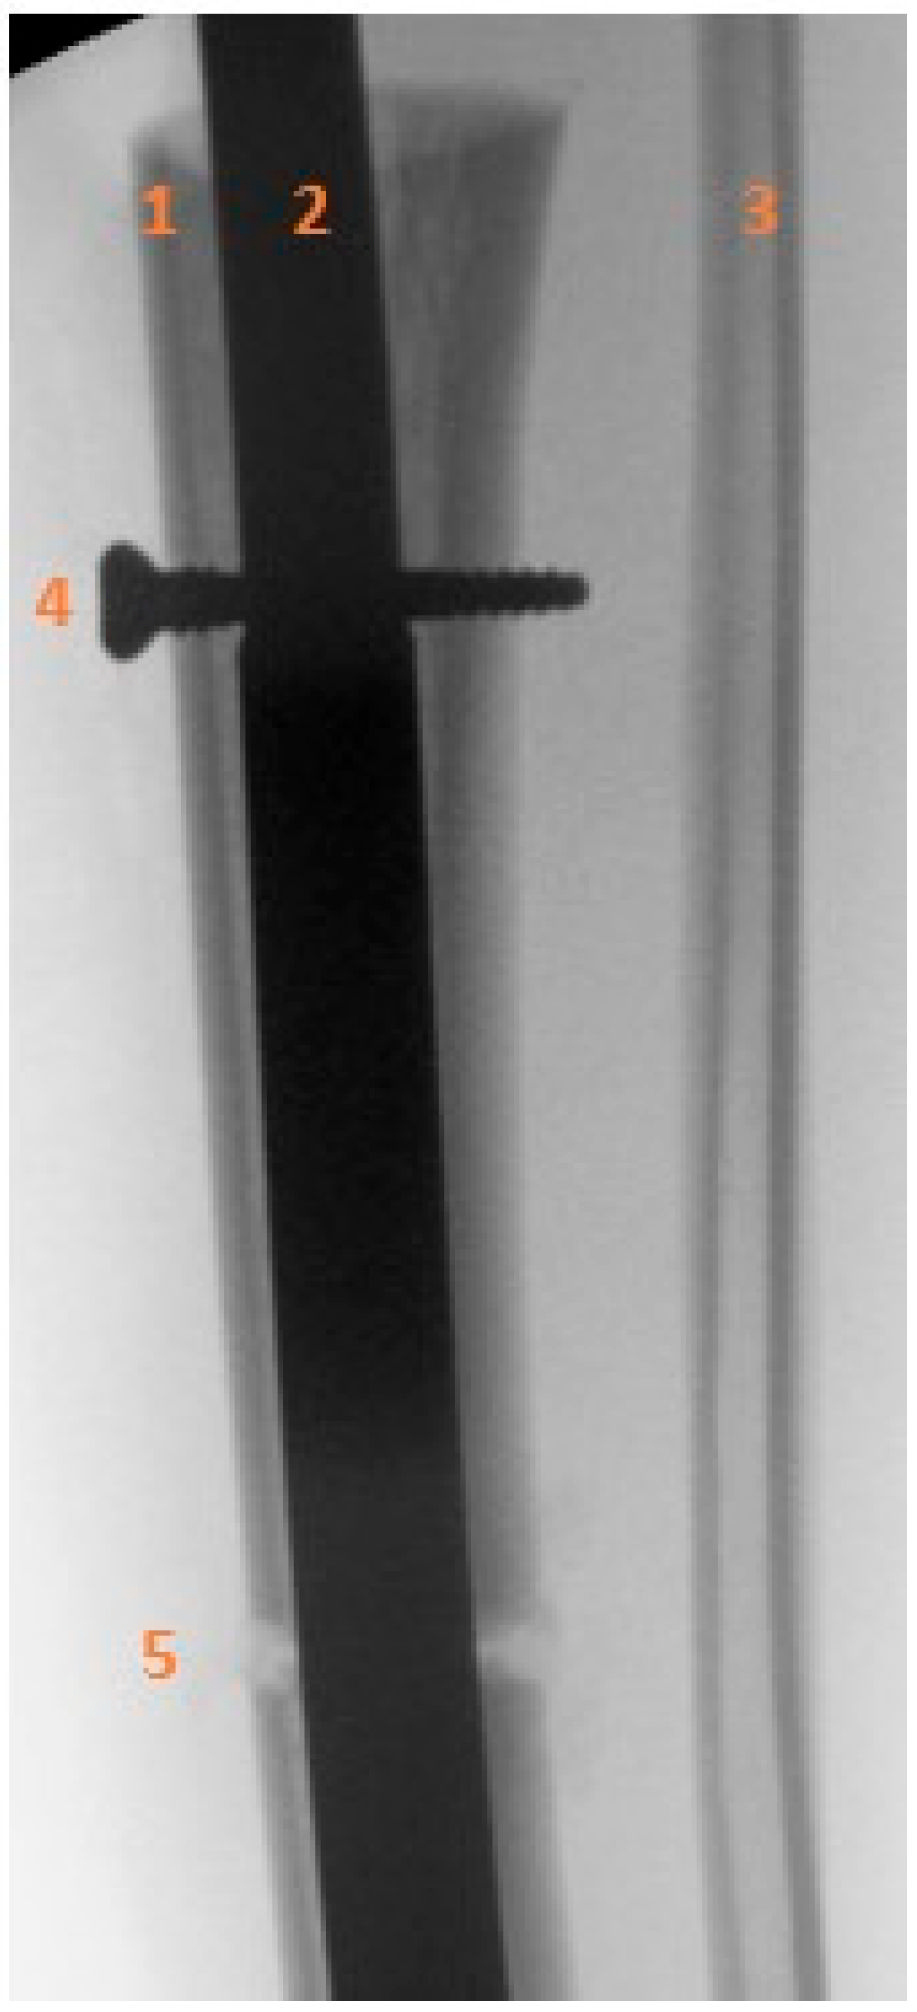

- Fixation of the transport segment: A locking bolt was inserted into the transport segment to engage the internal transport mechanism of the intramedullary nail (Figure 5).

Figure 5. Intraoperative anteroposterior radiograph showing the locking bolt inserted into the transport segment. (1) Proximal tibial diaphysis and transport segment. (2) Intramedullary nail. (3) Intact fibular diaphysis. (4) Locking bolt within the transport segment and internal motor of the intramedullary nail. (5) Distal tibia, osteotomy of the transport segment. - Nail locking: The nail was locked proximally and distally to achieve stable fixation.